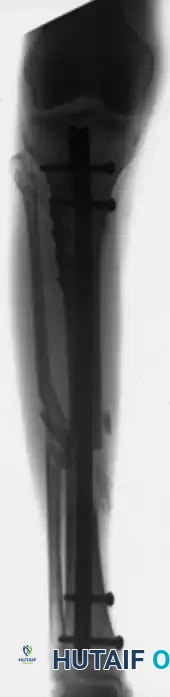

Intramedullary Fixation of Tibial Shaft Fractures

Locked intramedullary (IM) nailing is universally recognized as the gold standard and treatment of choice for the vast majority of type I, type II, and type IIIA open, as well as closed, tibial shaft fractures.

Biomechanical Advantages and Indications

IM nailing offers superior biomechanical advantages by acting as a load-sharing device positioned at the mechanical axis of the bone. This minimizes bending moments compared to eccentrically placed plates. Furthermore, IM nailing preserves the critical soft tissue sleeve and periosteal blood supply around the fracture site, promoting secondary bone healing via callus formation and allowing for early mobilization of adjacent joints.

The ability to lock the nails proximally and distally provides absolute control over length, alignment, and rotation in unstable, comminuted, or segmental fractures. Modern interlocking designs permit the stabilization of fractures located as far proximal as the tibial tubercle or as far distal as 3 to 4 cm proximal to the ankle joint plafond.